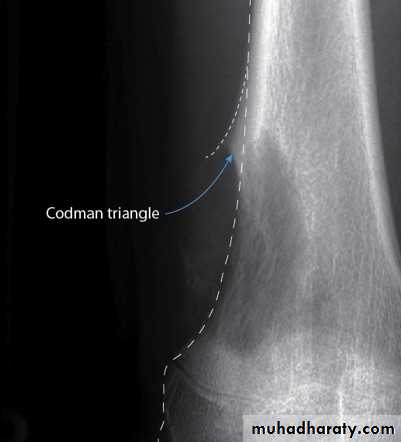

X-ray shows changes of bone destruction and new bone formation in the metaphysis (rarefaction + sclerosis).

Cortical perforation and soft tissue swelling.

Subperiosteal new bone formation sometimes in the form of Codmen’s triangle and/or sun burst appearance.